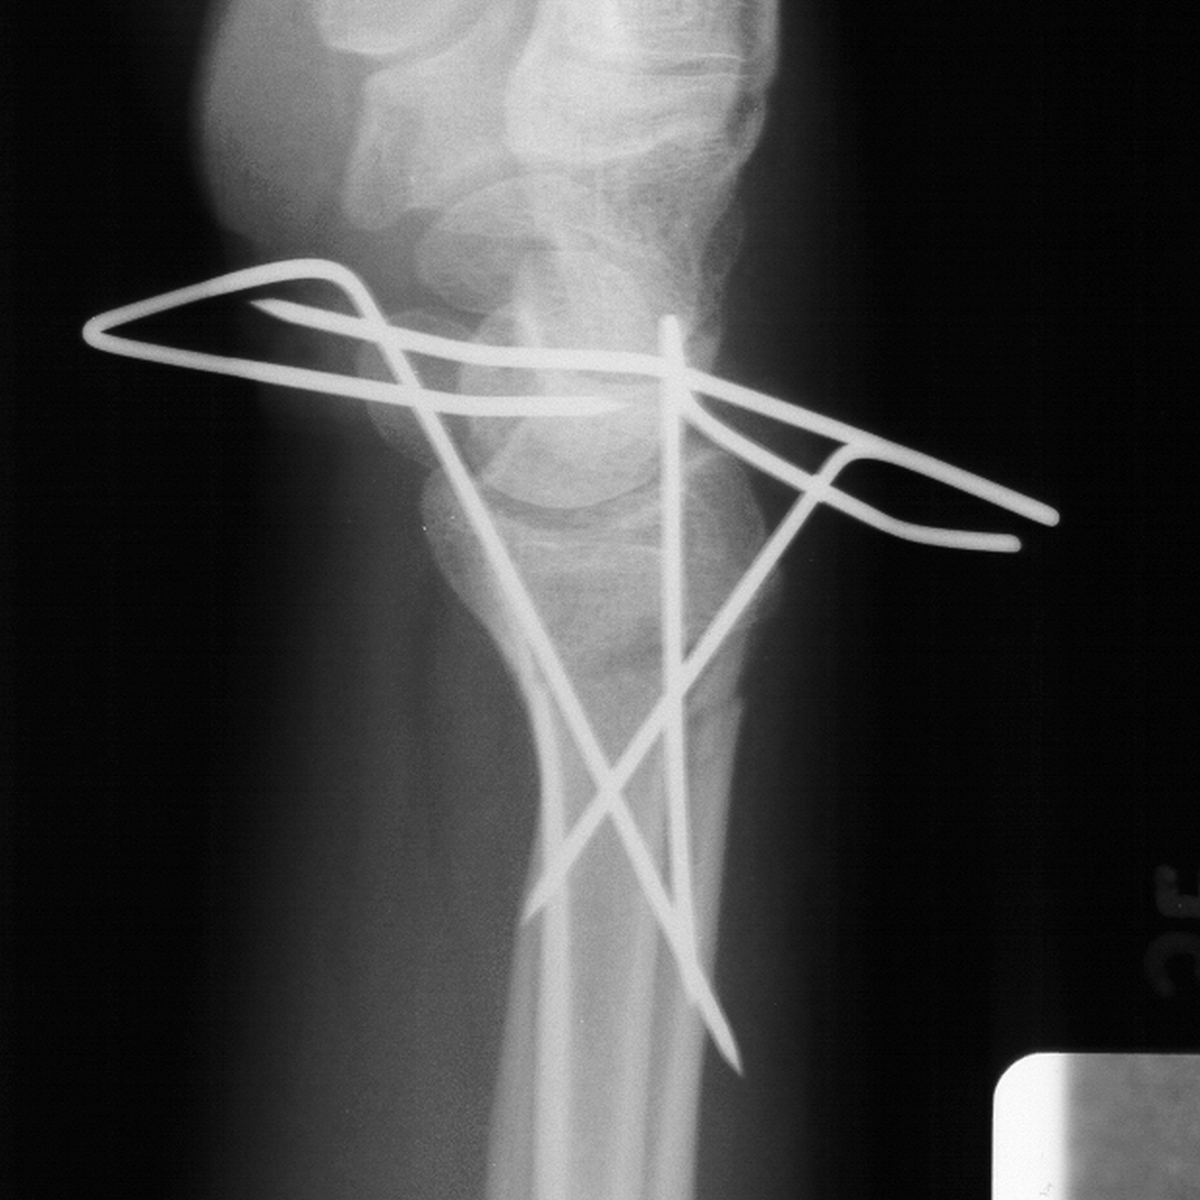

Rotated unstable spiral oblique proximal phalanx

fracture. |

| Reduction and fixation. |

| Appearance at four